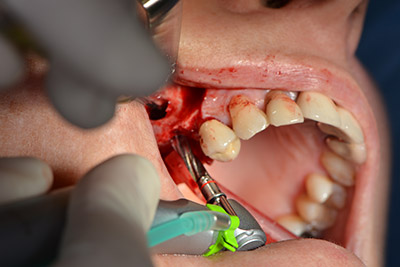

The next step was the sinus floor elevation with simultaneous implantation. The Implantmed also had a presetting at the first position for the buccal fenestration of the maxillary sinus wall.

The fenestration was prepared at 35,000 rpm and then the nasal mucosa were prepared in the cranial direction (Fig. 13 to 14).